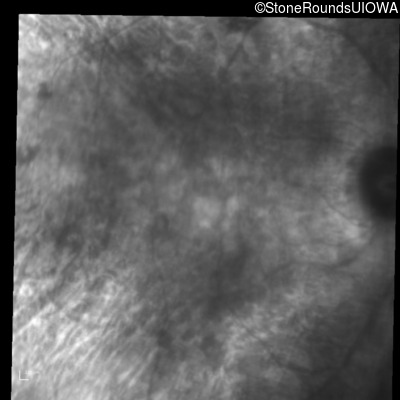

Infrared Fundus Photograph - Right - 20/25

Exemplar